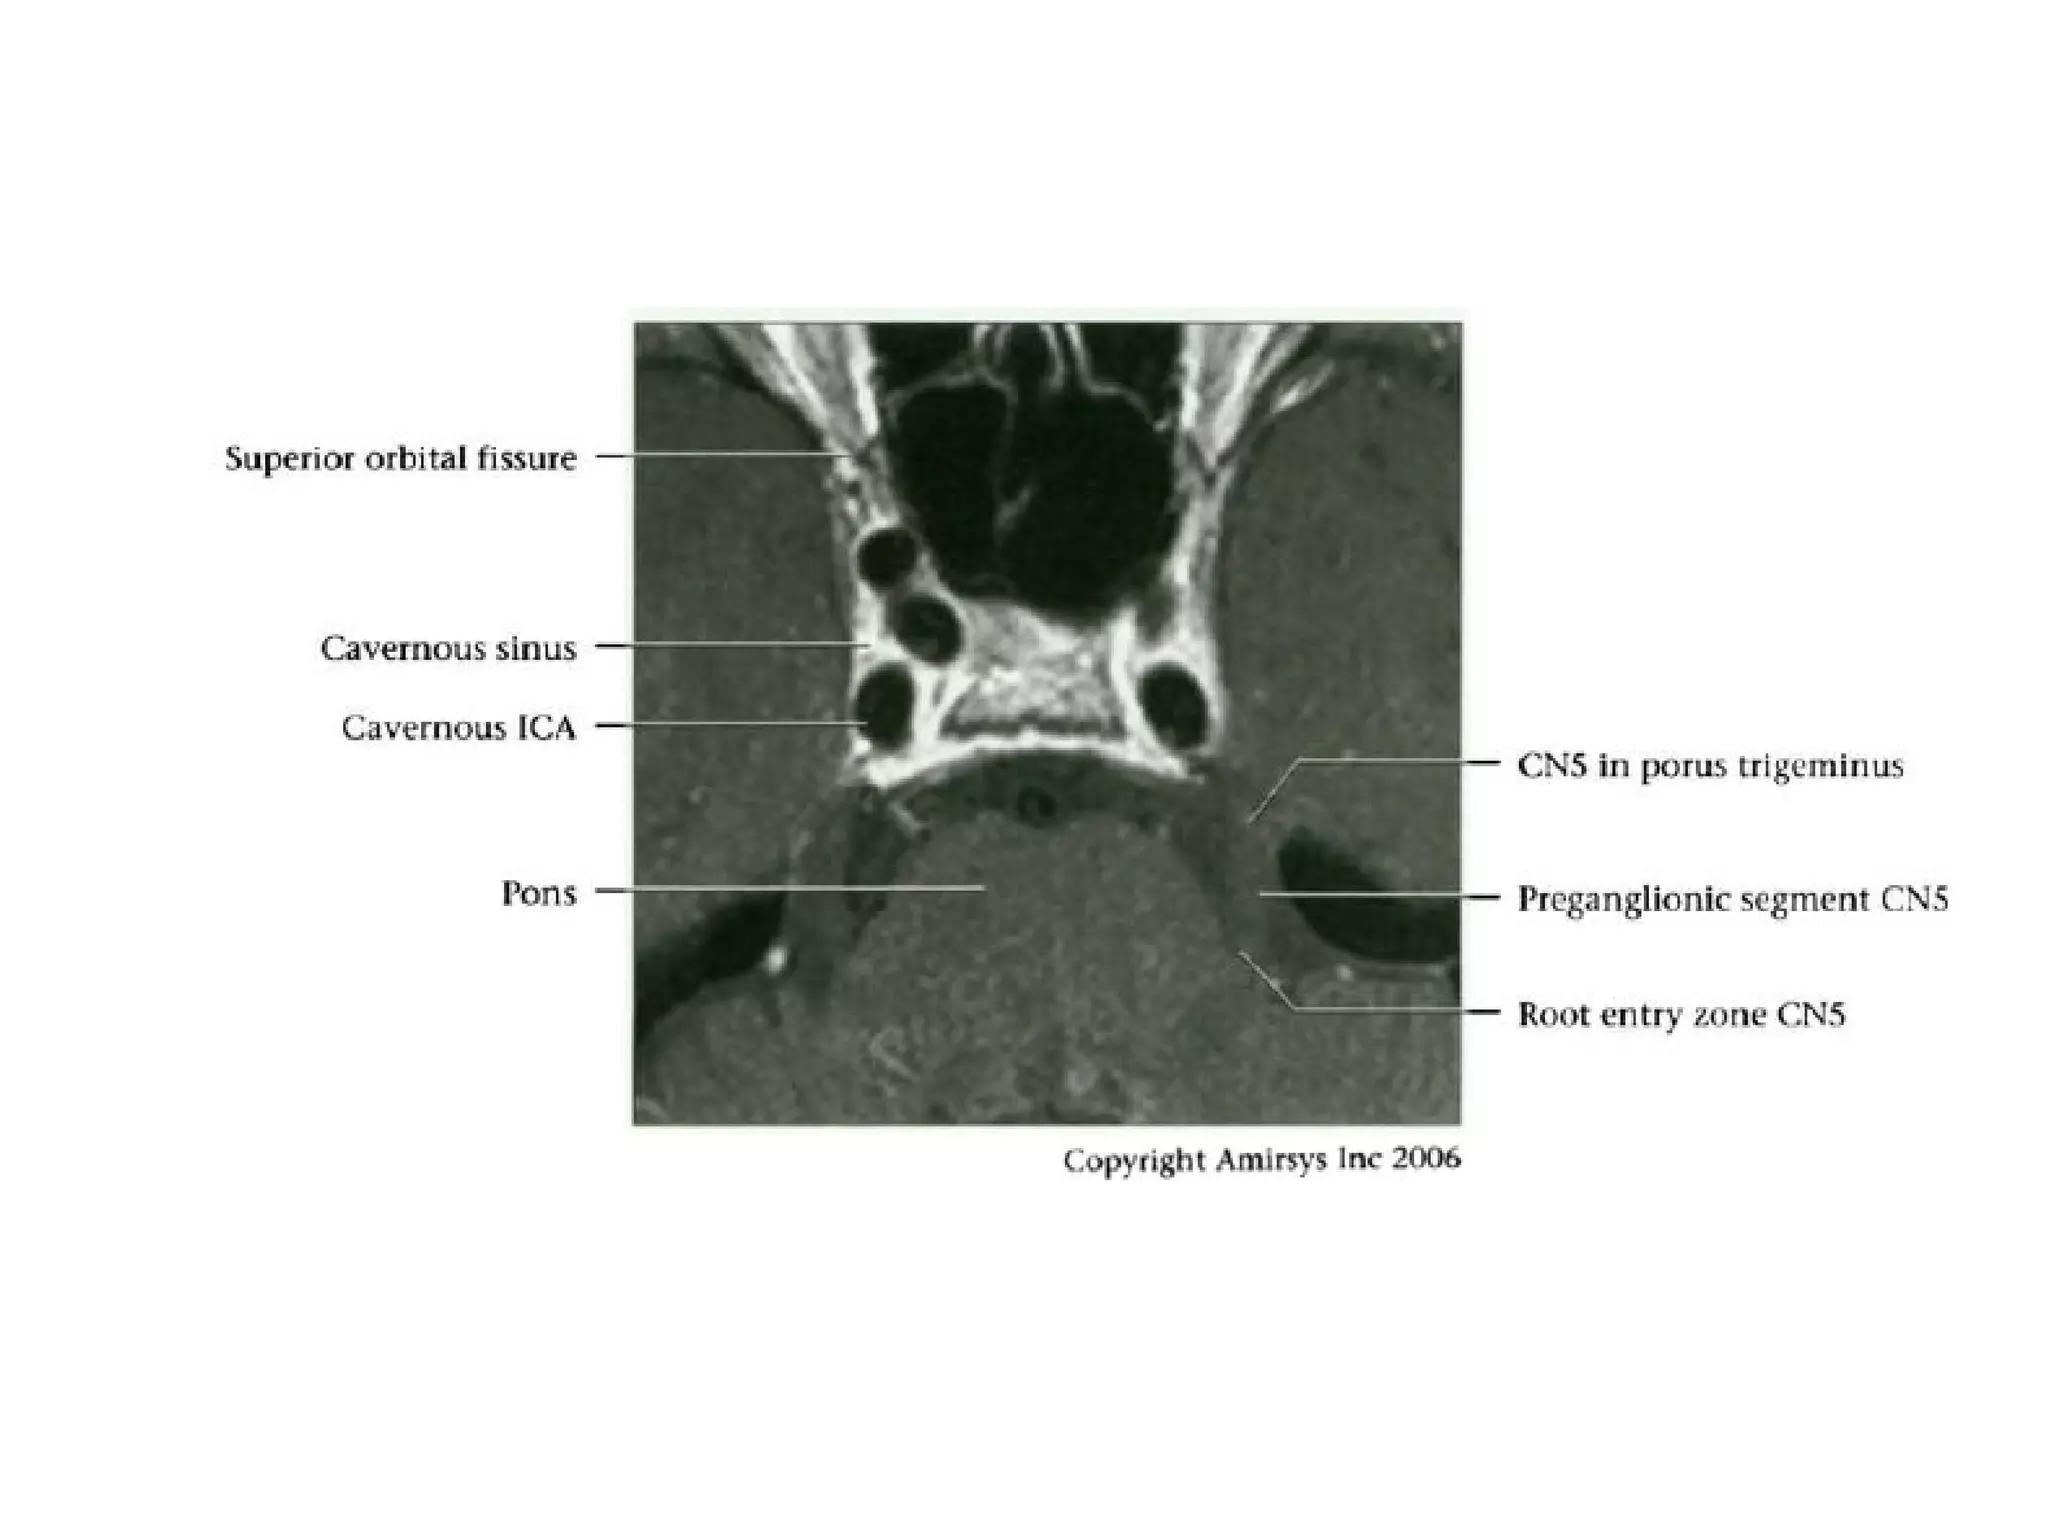

Cranial Nerve V:

The Trigeminal Nerve

• The trigeminal nerve is the largest cranial nerve.

• It is composed of a large sensory root that

runs medial to a smaller motor root.

• The roots emerge from the lateral midpons and

travel anteriorly through the prepontine cistern

and the porus trigeminus to the Meckel

(trigeminal) cave, a CSF-containing pouch in the

middle cranial fossa.

• Because the trigeminal nerve is large and its

course proceeds straight forward from the lateral

pons, it is easy to recognize on most MR

images.

RadioGraphics 2009; 29:1045–1055

• In the Meckel cave, the nerve forms a meshlike web that

can be visualized only with high-resolution imaging.

• Along the anterior aspect of the cavity, the trigeminal

nerve forms the trigeminal (gasserian) ganglion before

splitting into three subdivisions.

• The ophthalmic (V1) and maxillary (V2) divisions of the

nerve move medially into the cavernous sinus and exit

the skull through the superior orbital fissure and foramen

rotundum, respectively.

• The mandibular division (V3), which includes the motor

branches, exits the skull inferiorly through the foramen

ovale.